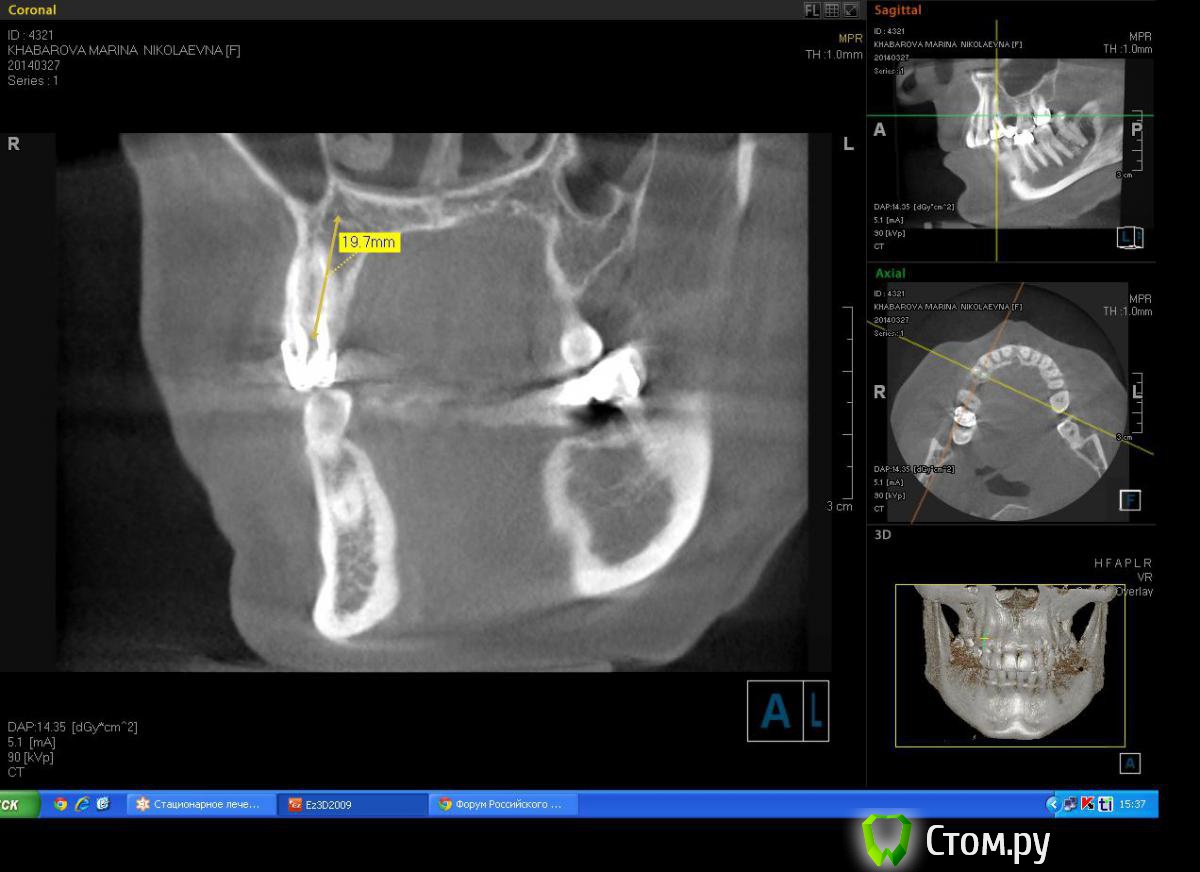

Milanomoda Опубликовано 22 апреля, 2014 Автор Поделиться Опубликовано 22 апреля, 2014 Картина с планируемым 4.2 х 16 мм имплантом в области 14. Ссылка на комментарий

DShu Опубликовано 22 апреля, 2014 Поделиться Опубликовано 22 апреля, 2014 4,2 думаю им там тесновато будет. 4,5 тем более.На 14 я бы поставил 3,75*16 (или на 13) на 15 - 3,75*10 бикортикально. Сразу формики, вокруг - графт или без него, кто как любит) 3 Ссылка на комментарий

Troy Опубликовано 22 апреля, 2014 Поделиться Опубликовано 22 апреля, 2014 4,2 думаю им там тесновато будет. 4,5 тем более.На 14 я бы поставил 3,75*16 (или на 13) на 15 - 3,75*10 бикортикально. Сразу формики, вокруг - графт или без него, кто как любит)Нормально там 4.2 будет. А так +100 На 14 4.2-13 притопив альфа-био миллиметра на 2, под ФДМ так как ставим в небный, а на 15 4.2-10 немного поработать остеотомом и установить бикортикально с ФДМ, Ушить без всякого графта и мембран, Все будет ОК Ссылка на комментарий

Milanomoda Опубликовано 28 апреля, 2014 Автор Поделиться Опубликовано 28 апреля, 2014 А можно увидеть замер расстояния между 13 и 16 и промеры толщины гребня? ИМХО, 4,2 в области премоляров - не самый лучший вариант и я не уверен, что "все будет ОК" Спасибо за беспокойство, в прошлую пятницу принимал даную пациентку. Вообщем в итоге при удалении зуба 14 произошел отлом щечной стенки, причем такой приличный, она была толщиной мне кажется тоньше чем листок бумажки. Вообщем в область 15 поставил 4.2\8, а лунку зуба 14 пришлось наполнять графтом(BondBone) и планировать отсрочено. Ссылка на комментарий